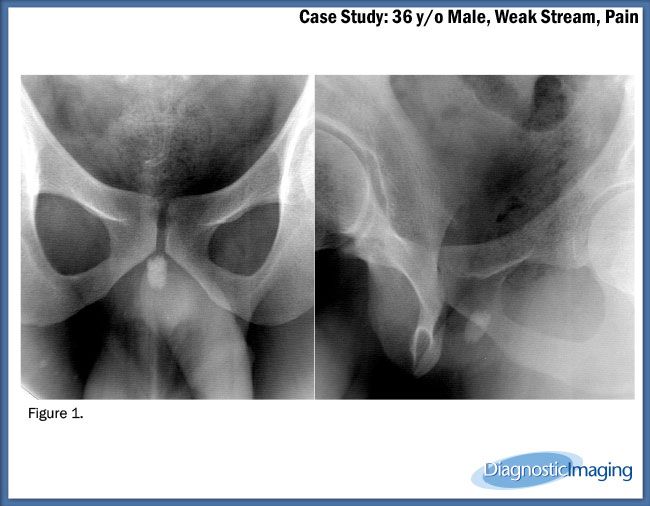

Case History: 36-year-old male presented with weak stream and pain.

Case History: A 36-year-old male presented with weak stream and pain.